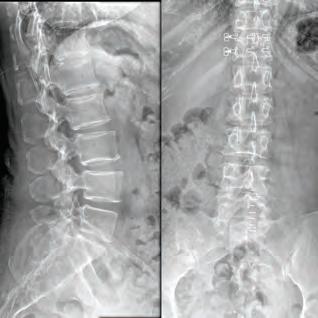

Stephen P. Courtney, MD

For board-certifid, fellowship trained orthopedic spine surgeon

Dr. Stephen P. Courtney, patients come fist. It’s an ethos that developed early on in his life and one that has helped guide him in his journey to earn a distinguished reputation among his professional colleagues, medical peers and, most importantly, his patients.

Inspired by the patients he’s cared for there, Dr. Courtney made education a priority. He was salutatorian of his high school class and went on to graduate summa cum laude from Northeast Louisiana University. While at Louisiana State University Medical School, he utilized his summer to perform spine biomechanical tests on human spine cadavers utilizing pedicle screws. Considered cutting edge biomechanics and technology at that time, most spine surgeons didn’t even know they existed yet. However, Dr. Courtney performed one of the fist biomechanical tests on those implants. It was a feat that earned him the Howmedica Biomechanic Award and the Louisiana Orthopedic Association Award. He also placed fourth in the World Congress for Student Research Competition.

Ths realization inspired Dr. Courtney to design, develop, biomechanically test, complete FDA testing and oversee quality control and validation on a host of tools he created. To date, Dr. Courtney has developed nine spinal product lines and obtained nine patents and 14 trademarks on spine related products.

Led by Dr. Courtney, the skilled team at Advanced Spine Center cares for patients with neck and back pain using a wide array of the most state-of-the-art tools and techniques—from conservative physical therapy and injection therapy—to advanced pain manage-

SPINE SURGEON PRACTICING FOR 28 YEARS.

ment, as well as surgical intervention. We employ the latest in minimally invasive spine surgeries, in addition to cutting-edge replacement technology. Incorporating both high tech and high touch, we get our valued patients back to their lives so they can enjoy all the activities they love.